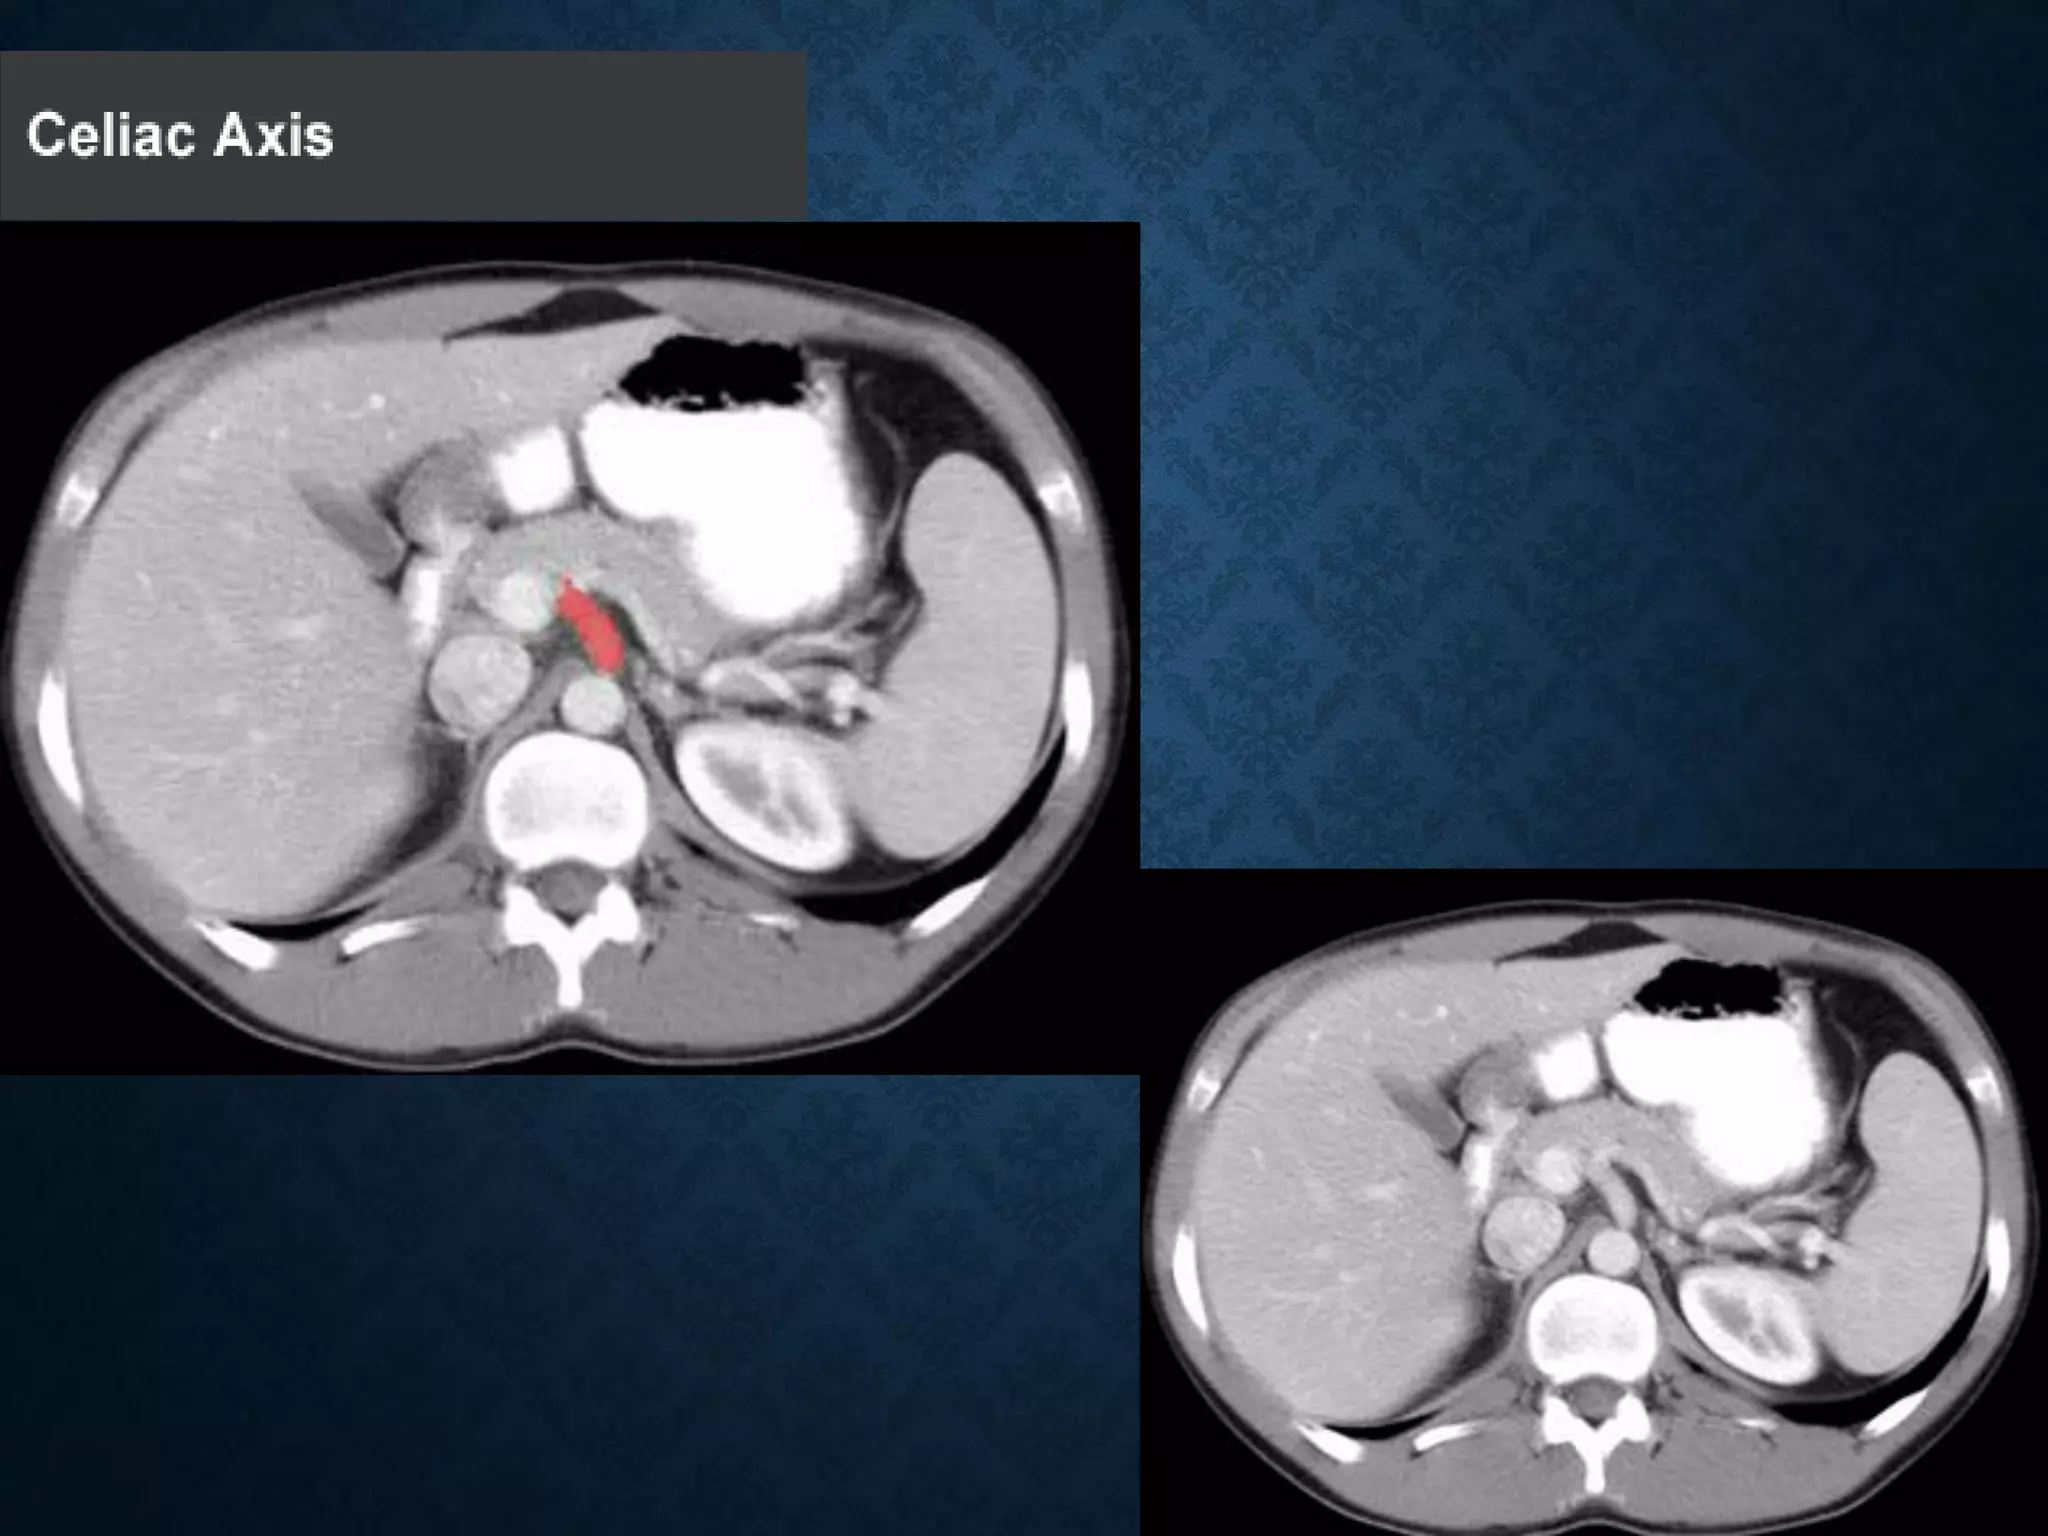

CELIAC

• Branching from the aorta 'anterior to the

T12‘ one of three anterior/ midline branches of the

abdominal aorta (the others are the superior and inferior

mesenteric arteries).

CELIAC ARTERY BRANCHES

• Left gastric artery

• Common hepatic artery

• Splenic artery

CELIAC • Branching fromthe aorta 'anterior to the T12‘ one of three anterior/ midline branches of the abdominal aorta (the others are the superior and inferior mesenteric arteries).

CELIAC ARTERY BRANCHES •Left gastric artery • Common hepatic artery • Splenic artery